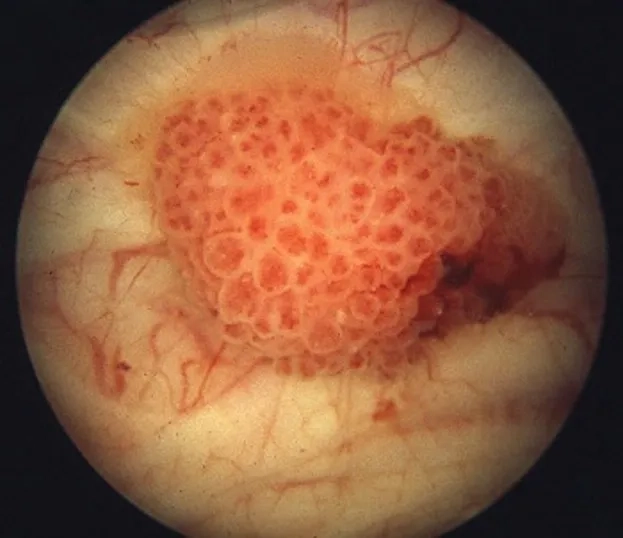

Transitional cell carcinoma, a type of bladder cancer